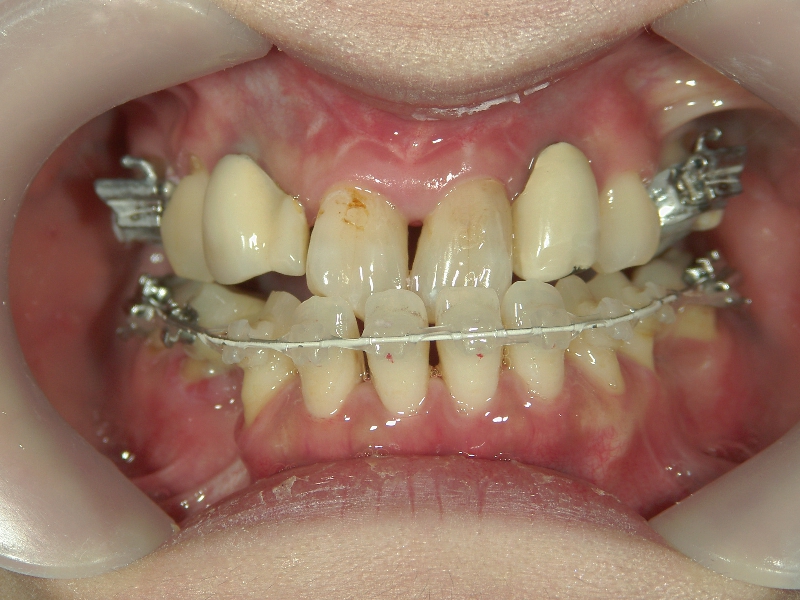

上の歯と下の歯を斜めに繋ぐようにツインフォースという装置を装着します。装置の力で、顎が前方へ押し出されてきました。

顎の移動が終了しました。装置を外して、今後はワイヤーを使用して歯列を治します。

矯正治療後の後戻りを想定して、あえて必要量を越えた顎の移動を行います。